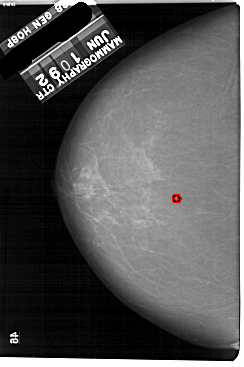

A_1864_1.LEFT_CC

LEFT_CC LINES 5491 PIXELS_PER_LINE 3646 BITS_PER_PIXEL 12 RESOLUTION 43.5 OVERLAY

FILE: A_1864_1.LEFT_CC.OVERLAY

TOTAL_ABNORMALITIES 1

ABNORMALITY 1

LESION_TYPE CALCIFICATION TYPE PLEOMORPHIC DISTRIBUTION CLUSTERED

ASSESSMENT 4

SUBTLETY 2

PATHOLOGY BENIGN

TOTAL_OUTLINES 1

BOUNDARY